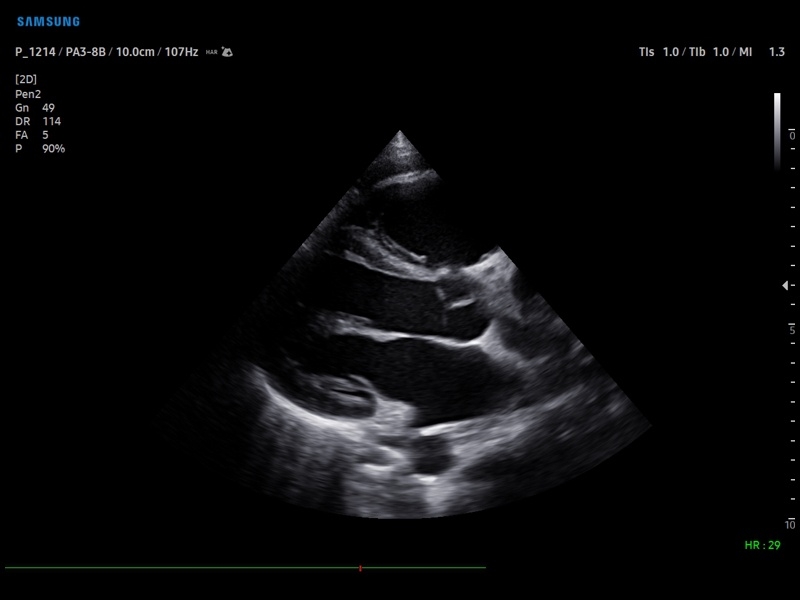

• Кардиология

• Кардиопакет: тканевый допплер (TDI) + анатомический М-режим + цветной М-режим (CM) + программное обеспечение.

• Пакет кардиологических исследований.

• Модуль Stress Echo – программа для исследования сердца под нагрузкой.